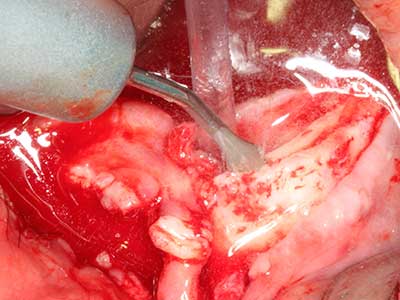

Indication: Preparation near nerves

As noted above, indications for piezosurgery can also be found in the field of conservative dental surgery. Special working tips simplify the exposure of root tips and make it easier to protect nerves and sinus mucous membranes, particularly in the lower premolar and upper posterior tooth regions. Angled diamond tips are used to precisely prepare the resection cavity for the retrograde root filler material for unsealed apical obturation. The ultrasonic technology means the tips can be very slender, which improves the view and the size of the access cavity. As a result, the application of ultrasonic surgery for this indication is one of the standard procedures for apical resection (Del Fabbro, Tsesis et al. 2010, Scarano, Artese et al. 2012).

Indication: Apical resection

When surgical procedures are performed on bone in the immediate vicinity of sensitive structures such as blood vessels or nerves, rotary instruments pose a significant risk of iatrogenic injury. Piezoelectric devices can be helpful for preparation of bone covers and removal of hard tissue close to nerves, particularly for exposure of nerves after iatrogenic injury but also during nerve lateralization for resective and reconstructive procedures or implant placement (Fig. 17-20). Light contact between the piezotip and the nerve does not generally result in damage but proceeding incautiously with saw-like motions or attachments where a residual bone substrate remains may cause temporary or even permanent nerve damage. However, the risk of damage is considered to be substantially lower than when using saws or milling instruments (Pereira, Gealh et al. 2014).